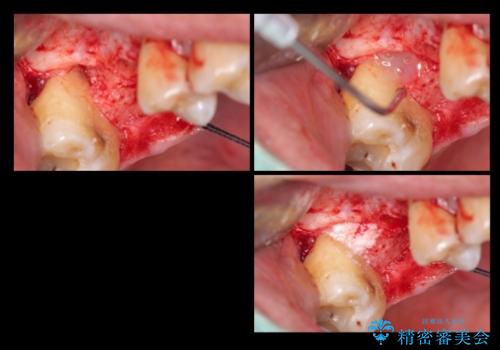

治療の内訳

左上6:インプラント(ストローマン)20万円、カスタムアバットメント10万円、スクリューリテイン仮歯2万円、ジルコニアクラウン10万円、ソケットリフト10万円、マイナーGBR 5万円、静脈麻酔(麻酔認定医)5万円